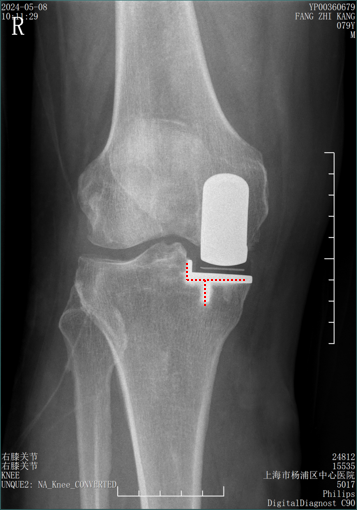

辨认bearing内的标识( X-ray正位)

bearing 内的标识:点和线段 “ .—. ” 线段显示为“—”在前;点显示为“.”在后

Bearing 中立位( X-ray正位)

Bearing 内旋( X-ray正位)

Bearing 外旋( X-ray正位)